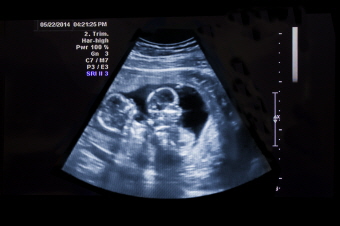

다태아(Multifetal pregnancy)

다태아는 둘 이상의 태아가 동시에 임신이 되는 상태를 의미합니다. 쌍둥이, 세쌍둥이, 네쌍둥이 등을 말합니다.

초음파 검사에서 두 명 이상의 태아가 확인될 뿐만 아니라 두 개 이상의 심음이 들립니다.

겉모습으로 볼 때 임신 주수에 비해 산모의 배가 클 경우 다태아를 의심합니다. 초음파상으로 태아가 한 명 이상인 것을 확인하면 다태아를 확진합니다.